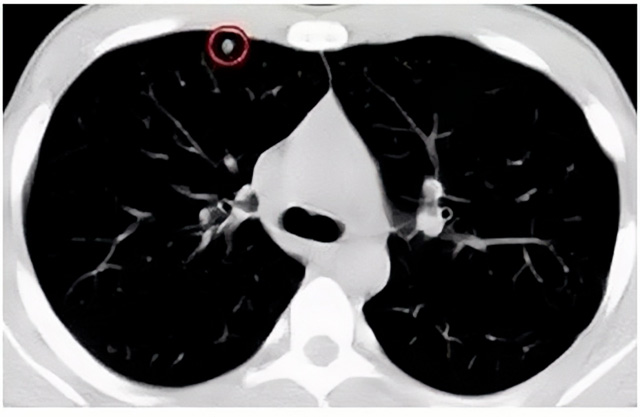

移動CT體檢車可以檢查肺結(jié)節(jié)發(fā)現(xiàn)早期肺癌

移動CT體檢車可以做肺部檢查。隨著多層螺旋CT肺部低劑量掃描的臨床應(yīng)用,目前很多人選擇肺部CT作為常規(guī)檢查項目,較大地提高了肺結(jié)節(jié)的檢出率。如果檢查發(fā)現(xiàn)肺部有肺結(jié)節(jié)是磨玻璃型的,小于5mm的微小結(jié)節(jié),大部分都是良性的。如果達到1CM以上的,很有可能有肺癌的機率。根據(jù)其內(nèi)密度不同可分為磨玻璃結(jié)節(jié)、實性結(jié)節(jié)、部分實性結(jié)節(jié)。根據(jù)其大小可分為肺大結(jié)節(jié)、小結(jié)節(jié)和微小結(jié)節(jié)。如果是炎癥性肺結(jié)節(jié),幾個月后復(fù)查有變化變小就不用做手術(shù)。如果CT再次復(fù)查結(jié)節(jié)沒有變化,沒有縮小就需要升級做病例檢查。病理檢查的確診性是最高的。是有沒患癌的標(biāo)準(zhǔn)。檢查發(fā)現(xiàn)早的話,規(guī)范手術(shù)治療,手術(shù)后5年的存活率很高的。肺癌這個要早發(fā)現(xiàn)早治療。

現(xiàn)在的移動CT體檢車的分辨率比X光高,CT掃描的圖像越來越薄顯像更清晰,檢查更準(zhǔn)確。得到了普及,肺結(jié)節(jié)的測出率很高的。但是顯浩告訴大家,肺結(jié)節(jié)不等于肺癌。雖然很多是良性,但是很多肺癌都是肺結(jié)節(jié)發(fā)展來的。 必須定期檢查復(fù)查。磨玻璃結(jié)節(jié),肺癌的機率較高。肺癌是惡性腫瘤病死率最高的。除了環(huán)境,遺傳,等因素。吸煙,從事煙霧工作行業(yè)的人員比較危險。發(fā)病比例高。肺部疾病早發(fā)現(xiàn)早治療,依舊是肺部疾病的治療標(biāo)準(zhǔn)。

一旦CT檢查發(fā)現(xiàn)肺結(jié)節(jié),若不規(guī)律復(fù)查,檢查等同于白檢。所以在復(fù)查中,如果結(jié)節(jié)中發(fā)現(xiàn)有增大的趨勢,或大小發(fā)生了變化,我們必須提請注意及時治療,不要掉以輕心。移動CT體檢車的普及化,讓肺部檢查更準(zhǔn)確更高效。發(fā)現(xiàn)肺結(jié)節(jié)時,及時就醫(yī)并進行專業(yè)評估是確保準(zhǔn)確分類和采取適當(dāng)措施的關(guān)鍵。